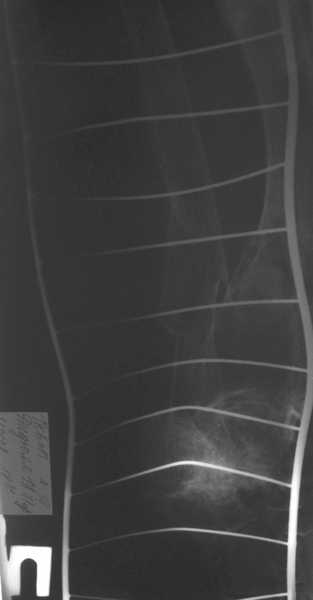

Травма в результате ДТП. (Пациентка передвигалась на инвалидной каляске и была сбита автомобилем). Диагноз: Множественная травма. Перелом нижней трети правого бедра. Перелом средней трети правой б/берцовой, малоберцовой кости, нижней трети левой большоберцовой, м/берцовой кости.Травматический шок. Со стороны внутренних органов и систем без патологии. Больная госпитализирована в реанимационное отделение, где было наложено двойное скелетное вытяжение за правую н/конечность. Левая н/конечность иммобилизована гипсовой лонгетой.

Из анамнеза: больная является инвалидом 1 группы по опорно-двигательному аппарату. В детстве перенесла рахит. Осложнением которого "О" образная деформация нижних конечностей. Ограничено отведение нижних конечностей, деформирующий артроз тазобедренных и коленных суставов. В 1990 году перелом правого бедра остеосинтез пластиной. После операции больная передвигалась только на костылях или в инвалидной коляске.

Прошу прощения за качество снимков. Р-графия производилась в реанимационном отделении передвижным аппаратом.